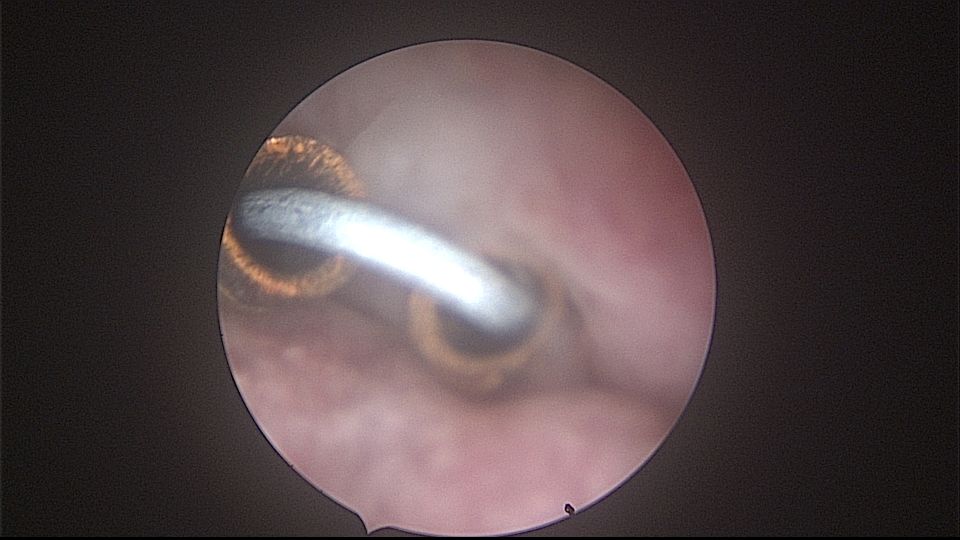

患者52岁,G2P1,顺产1次。安环27年,外院取环失败。病人肥胖,B超提示子宫前位,节育环距宫底0.9cm。子宫极度前倾前屈位,宫腔镜见宫颈管组织杂乱,宫颈管上段右前壁见假道,膨宫不良,视野模糊,寻找宫腔方向困难,准备B超监护过程中,拆走扩阴器,腹部下压子宫,终于寻找到了宫颈内口,看到了爱母环下端,异物钳牵拉出节育环,再次探查宫腔,无其他异常。